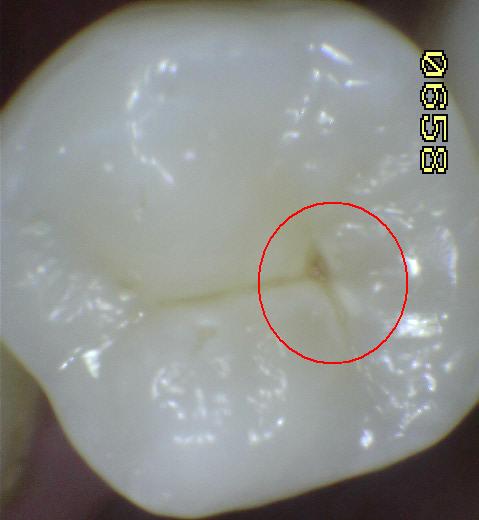

Una morfología de la fisura estrecha, con forma de botella de "Coca-Cola" genera un nicho ecológico ideal para la colonización de cualquier bacteria productora de ácidos. Al no poder remover en forma períodica dicho biofilm de una zona tan estrecha, el ataque ácido genera una lesión cariosa en la dentina, con un aspecto de esmalte intacto a la inspección visual, o sea un típico código 3 y 4 de ICDAS Completo. (Caries Moderada para el ICDAS COMBINADO)

Código 3 (Caries moderada) in vitro. Los códigos 3 in vivo debe ser sellado para evitar el avance del proceso carioso. (MNO)

Código 4 (Caries moderada) in vitro. Los códigos 4 in vivo deben ser tratados en forma operatoria con preservación dental (MOPD), porque presentan dentina infectada.

El examen visual debe emprenderse con los dientes completamente secos y con una buena iluminación.  El uso de amplificación de imagen también puede ayudar en el diagnóstico. El uso de una sonda se restringe al levantamiento de placa y detritos de comida.

El diente al lavarse y secarse con la jeringa triple deja expuesto esmalte blanquecino escarchado o opaco que delata un proceso de desmineralización, debido a que el agua se evapora de los microporos. Ver círculos rojos

Una mancha oscura de dentina que se observa a través del esmalte intacto,  adyacente a la fosa y reborde marginal,  indica la presencia de desmineralización. (Imagen 0229)